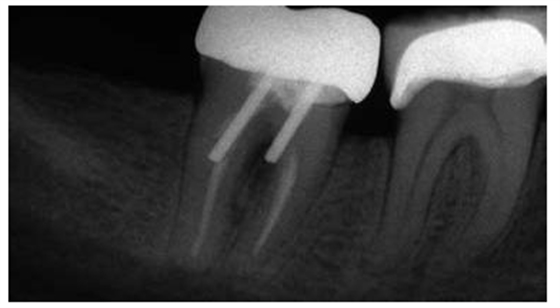

圖1:上頜第二前磨牙根折的根尖片,經(jīng)由預(yù)成金屬樁修復(fù)

圖2:上頜第一前磨牙的根尖片,過(guò)長(zhǎng)的平行壁樁修復(fù),根尖部的牙膠量少于理想的5mm的根尖封閉

在根尖片上,根管內(nèi)牙膠的最短長(zhǎng)度應(yīng)當(dāng)是5mm以確保充足嚴(yán)密的根尖封閉。

牙髓治療后的牙齒經(jīng)過(guò)樁道的預(yù)備,根尖部的牙膠是抵抗根尖周區(qū)域細(xì)菌傳播的屏障。許多研究結(jié)果都已經(jīng)證實(shí)當(dāng)根尖部的牙膠長(zhǎng)度僅僅是2mm到3mm時(shí),根管內(nèi)存在嚴(yán)重的滲漏;根尖部牙膠量為4mm到5mm能保證充足的根尖封閉。盡管多數(shù)研究結(jié)果都表明4mm的根尖牙膠量能提供充足的根尖封閉,但是樁道預(yù)備時(shí)要精確地達(dá)到4mm是非常困難的,根尖片拍攝角度的差異可能會(huì)導(dǎo)致根尖部保留的牙膠少于4mm。因此在根尖片上,根尖部牙膠5mm比4mm更為對(duì)根尖封閉安全有效。

除了磨牙之外,所有牙齒理想的樁長(zhǎng)度是由保存根尖部5mm牙膠封閉來(lái)決定的,同時(shí)將樁與牙膠嚴(yán)密接觸。對(duì)于磨牙而言,僅僅是首選根管應(yīng)當(dāng)被使用,同時(shí)樁進(jìn)入根管內(nèi)的長(zhǎng)度不能超過(guò)7mm。應(yīng)當(dāng)避免使用短樁。

盡管短樁從未被提倡使用,但是研究發(fā)現(xiàn)經(jīng)常能在根尖片上觀察到短樁的存在(圖 3)。臨床上發(fā)現(xiàn)在327例樁修復(fù)當(dāng)中,僅僅有34%的樁長(zhǎng)度與冠上切-頸長(zhǎng)度相當(dāng),即冠與樁長(zhǎng)度的比例為1:1。一項(xiàng)研究曾對(duì)200例牙髓治療后的牙齒進(jìn)行評(píng)估,結(jié)果顯示僅僅14%的樁長(zhǎng)度為牙根長(zhǎng)度的2/3或者長(zhǎng)于牙根長(zhǎng)度的2/3。另外一項(xiàng)根尖片研究結(jié)果表明樁修復(fù)中,樁長(zhǎng)度為牙根長(zhǎng)度的2/3或者3/4的比例僅占5%。當(dāng)臨床上應(yīng)用短樁修復(fù)時(shí),由于高應(yīng)力的原因,牙根常常會(huì)發(fā)生折斷,反之,增加樁的長(zhǎng)度能夠提高牙根的抗折能力。

因此,長(zhǎng)度為牙根長(zhǎng)3/4的樁能夠提供最強(qiáng)的剛性,同時(shí)保證產(chǎn)生最小程度的牙根偏轉(zhuǎn)。盡管如此,對(duì)于多數(shù)牙齒而言,按照此表面的理想樁長(zhǎng)度原則進(jìn)行操作是非常困難的。當(dāng)一顆牙齒具有牙根平均長(zhǎng)度或者短于平均長(zhǎng)度的牙根時(shí),同時(shí)修復(fù)的樁長(zhǎng)度占據(jù)牙根長(zhǎng)度的2/3或者更長(zhǎng),在此情況下,就不能保存5mm的根尖牙膠封閉。因此,理想的樁長(zhǎng)度是由保存根尖部5mm牙膠封閉來(lái)決定的,同時(shí)將樁與牙膠嚴(yán)密接觸。